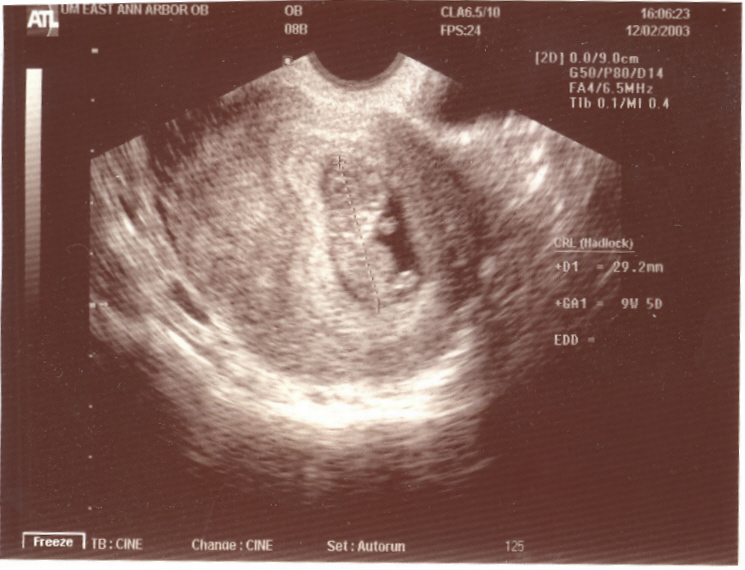

Previous Our Tiny Baby Next